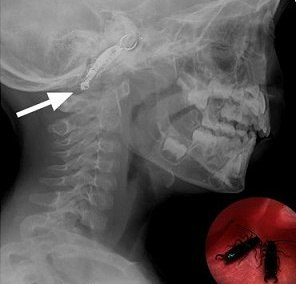

Одна женщина заснула на пляже, крошечная уховёртка заползла ей в ухо. Через несколько дней женщина пришла к врачу с ужасной болью в ухе. Осмотрев её ухо, доктор сказал: «Я ничего не вижу, вам нужно сделать рентген”. После того, как доктор получил снимки, он пригласил её вместе с мужем к себе в кабинет.

“Прежде всего, я хочу, чтобы вы сохраняли спокойствие. Уховёртка забралась вам в ушной канал. Мы не можем добраться до неё. Единственное, что нам остаётся, подождать пару недель, пока она прогрызёт себе путь сквозь ваш череп и выберется наружу из другого уха. И с вами всё будет в порядке”.

“Давайте сделаем ещё один рентген”,- сказал доктор. На этот раз женщина с мужем прождали немного больше, прежде чем доктор снова пригласил их в кабинет.

“Я боюсь, мне придется изменить диагноз”,- сказал доктор. “Я осмотрел уховертку и снимок рентгена”. Он сделал глубокий вдох. “Это была самка. Должно быть, она была беременна, когда залезла в ухо. Она отложила яйца в вашем черепе. Когда из яиц вылупятся молодые уховертки, они сожрут ваш мозг”.